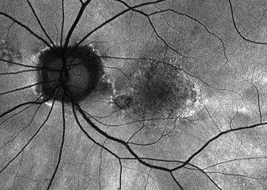

Multifocal lesions often grow faster than unifocal lesions6

Extrafoveal lesions often progress faster than foveal lesions6

Patients with bilateral GA often progress faster than those with unilateral GA6,7

Hyperfluorescence on FAF imaging is often correlated with faster lesion progression6